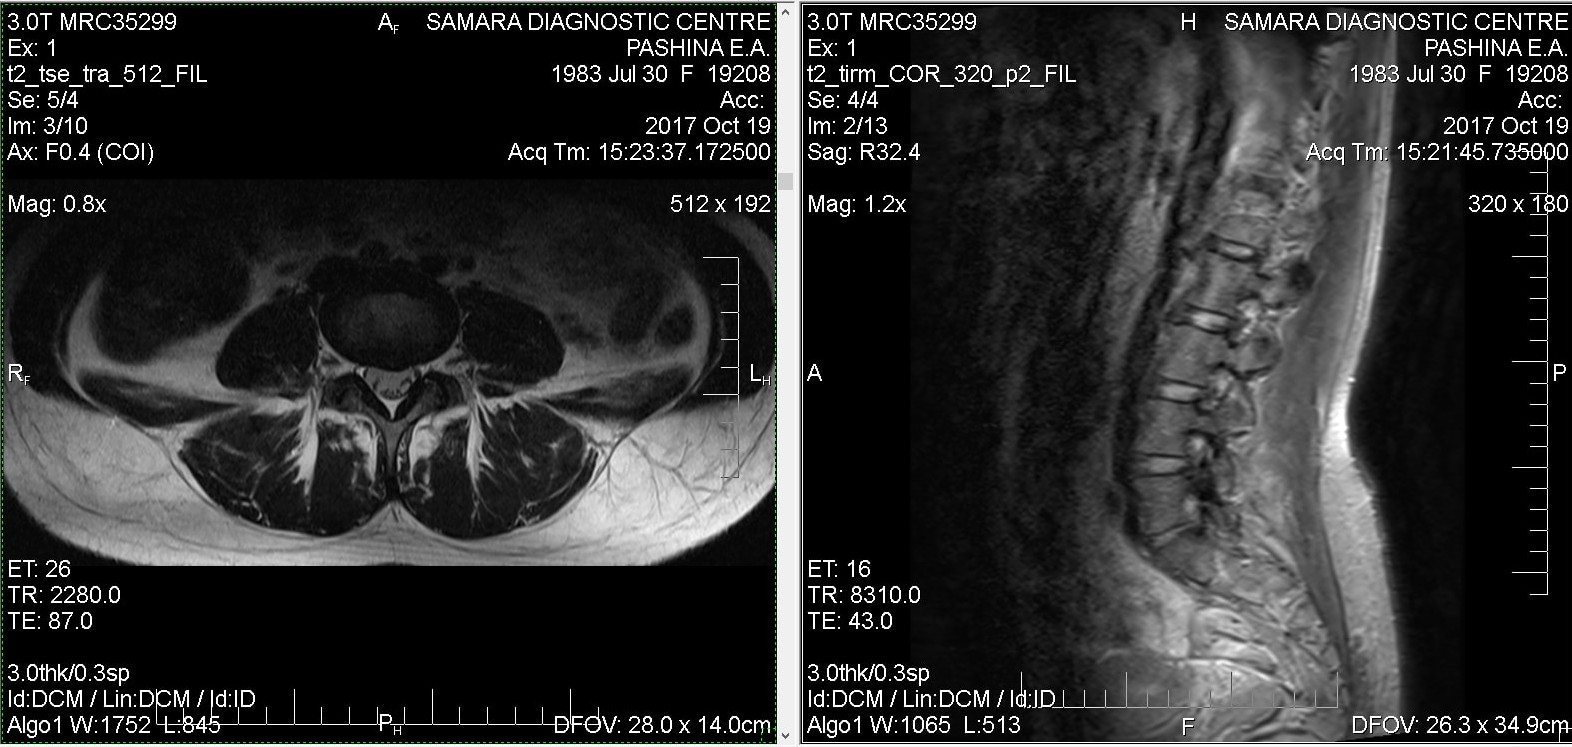

Тренировки с межпозвоночной грыжей.